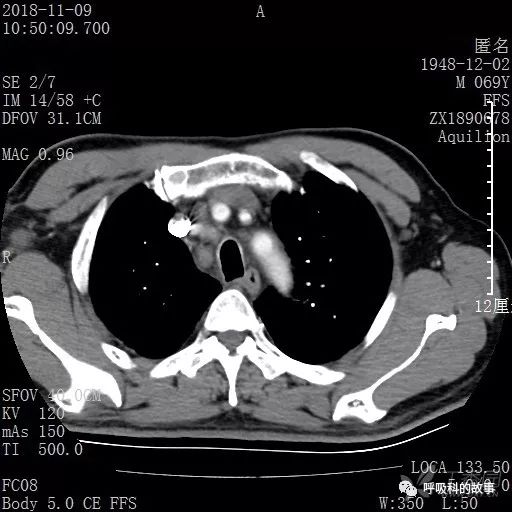

胸部增强CT示右肺门占位伴远端阻塞性肺炎,纵膈、右肺门、右侧颈根部、右侧腋下及肝门部肿大淋巴结。两侧胸腔少量积液。

肺窗CT